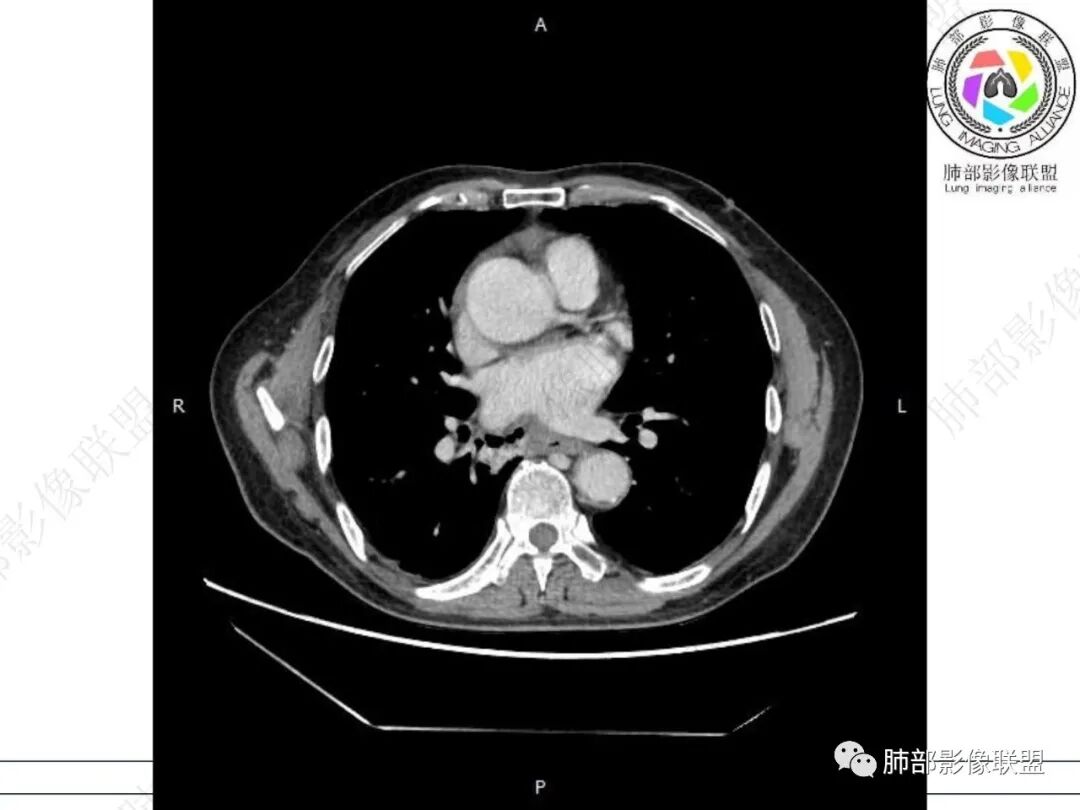

右肺下叶沿肺叶肺段分布斑片、条片状影,以下叶背段为显,边缘模糊,内可见支气管走行,局部支气管管壁增厚,右侧胸腔少量积液。纵隔隆突下可见不均匀软组织密度影,与周围结构分界不清,内见气体密度影,与食管及相邻右肺支气管之间未显示通道。邻近食管下段壁明显不规则增厚,增强后食管管壁明显不均匀强化,可见线样强化的连续完整粘膜影。

3.综合分析:

右肺下叶片影,气道相关,符合感染性病变。纵隔隆突下软组织密度影,异常气体影,长病程,起病缓慢,提示存在气管或食管瘘。食管镜未见明显新生物形成,临床未提供进食或饮水呛咳临床表现,综合分析应该考虑支气管瘘的形成。